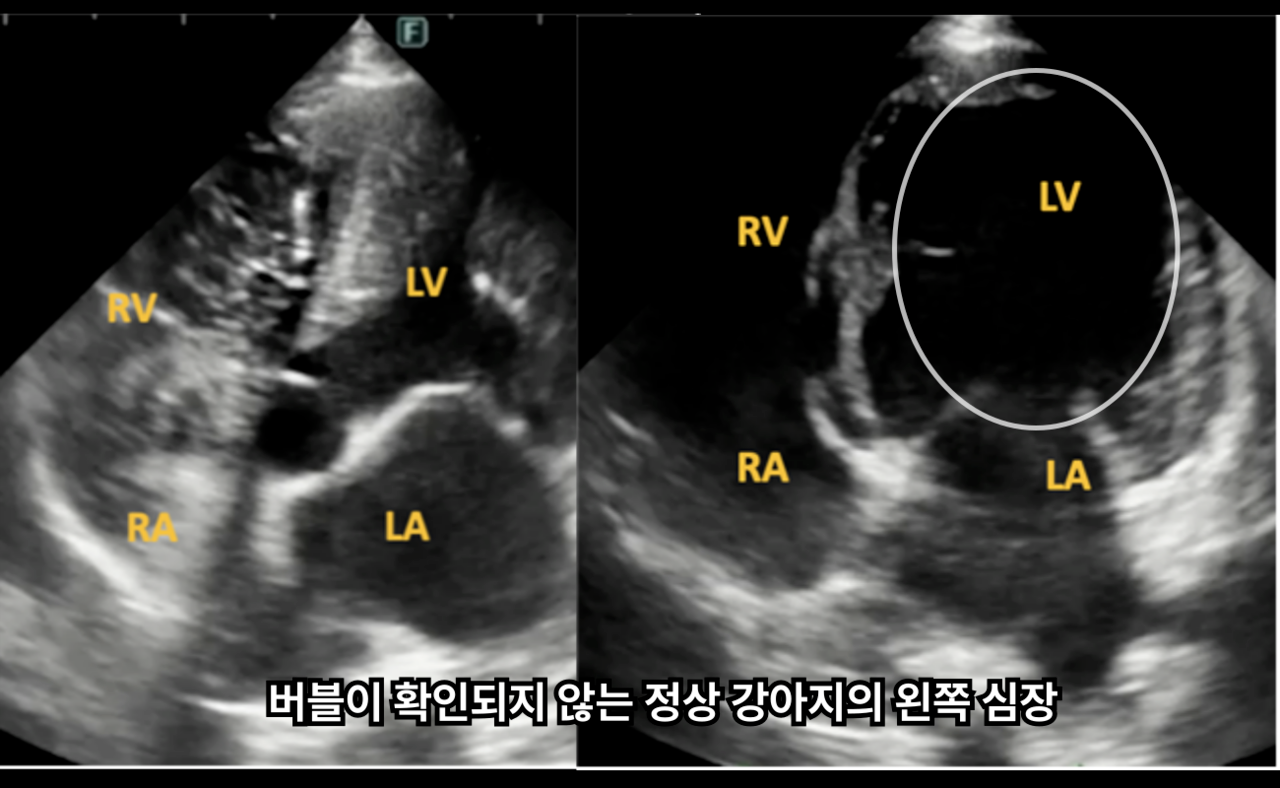

버블 에코는 반려동물의 심장 안 혈류 흐름을 미세한 공기방울(버블)로 시각화하여, 심장 내부에 숨겨진 비정상적인 통로가 있는지 구조적인 이상을 확인하는 특수한 심장 초음파 검사법입니다.

이를 통해 평소에는 별다른 이상이 없어 보이더라도,

혈액이 비정상적인 방향으로 흐르고 있지 않은지

확인할 수 있습니다.